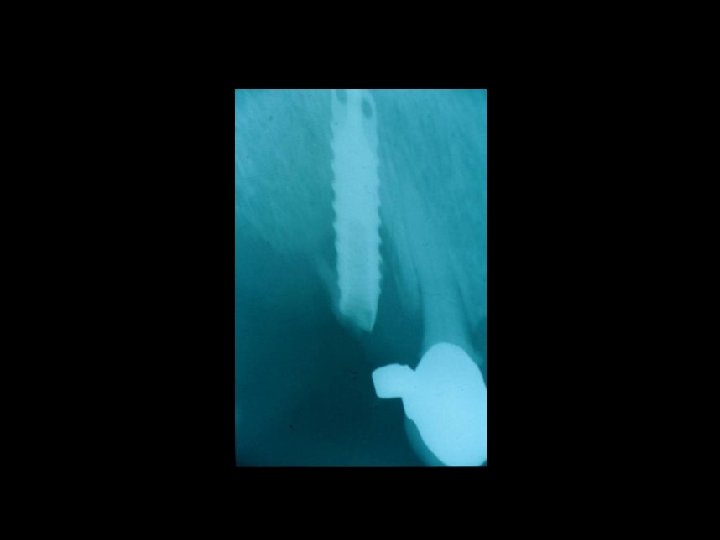

Responsabilità Ø Restauro della corona del dente Ø Trattamenti radicolari